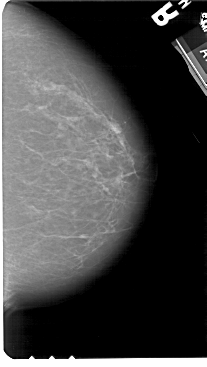

A_1273_1.RIGHT_MLO

RIGHT_MLO LINES 5491 PIXELS_PER_LINE 3016 BITS_PER_PIXEL 12 RESOLUTION 43.5 NON_OVERLAY